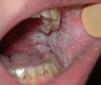

Piel. Formación continuada en dermatología Nevo blanco esponjoso familiar

Nevo blanco esponjoso familiar

Familial white sponge nevus